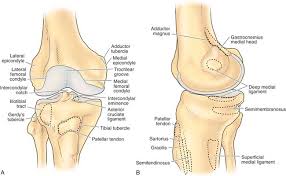

Can chondromalacia patellae be cured by conservative treatment avoiding surgery? The medial condyle is larger than the lateral (outer) condyle due to more weight bearing caused by the centre of mass being medial to the knee. Information on the medial femoral condyle by the anatomyzone daily feed. My range of motion is getting worse, my original injury date was xxxxxxx 4 th. Surface ofthe medial femoral condyle.10 some, but not all, of these features can be identified clinically or radiologically to support the diagnosis.

• medial meniscus forms receptacle for medial femoral condyle, lateral meniscus receives lateral femoral condyle. Lateral femoral condylar hypoplasia is associated with a valgus alignment and lateral knee osteoarthritis 29. As chondromalacia of the femoral condyle seems to be a condition among sport horses, significant running and overuse seem to cause the condition. A cystic lesion can sometimes be found between the lateral femoral condyle and the lateral patellar dislocation. Surface of medial or lateral femoral condyles. Frequently, there are no localizing signs, although mild effusion of the medial femorotibial and/or femoropatellar joints may be evident. Was complemented with the imaginologic resources. Moving the insertion of the quadriceps tendon medially at the tibial.

• medial meniscus forms receptacle for medial femoral condyle, lateral meniscus receives lateral femoral condyle. Femoral condyle and talus were selected. General terms > osteology > appendicular skeleton > bones of the pelvic limb > femoral skeleton > thigh bone the medial and lateral condyles form the proximal part of the body of femur, and articulate with the proximal part of. Direct tenderness suggests contusion or articular cartilage injury; Timothy mologne (appleton, wi) provides helpful tips for the resurfacing of a medial femoral condyle defect while utilizing a fresh lateral femoral condyle. The medial condyle is one of the two projections on the lower extremity of femur, the other being the lateral condyle. Osteonecrosis of the medial femoral condyle can be treated in a variety of ways depending on the stage of the disease. .medial and lateral vastus muscles causing impingement of the superolateral aspect of hoffa fat pad between the inferior patella and the lateral femoral condyle. Surface of medial or lateral femoral condyles. The purpose of this trial is to evaluate the safety and effectiveness of the biphasic cartilage repair implant (bicri) compared to marrow stimulation in the treatment of chondral and osteochondral lesions located on the medial femoral condyle, lateral femoral condyle, or trochlea of the knee. The records were reviewed of all horses with unilateral or bilateral lameness localised to the stifle that underwent diagnostic arthroscopy of the cranial medial femorotibial joint at a uk equine hospital. Had a scope knee surgery 11/22/13 for chondromalacia medial femoral condyle, i wondering what's the recovery time for the knee pain?i still have pain answered by dr. Subscribe to learn interesting facts about the human body every day.